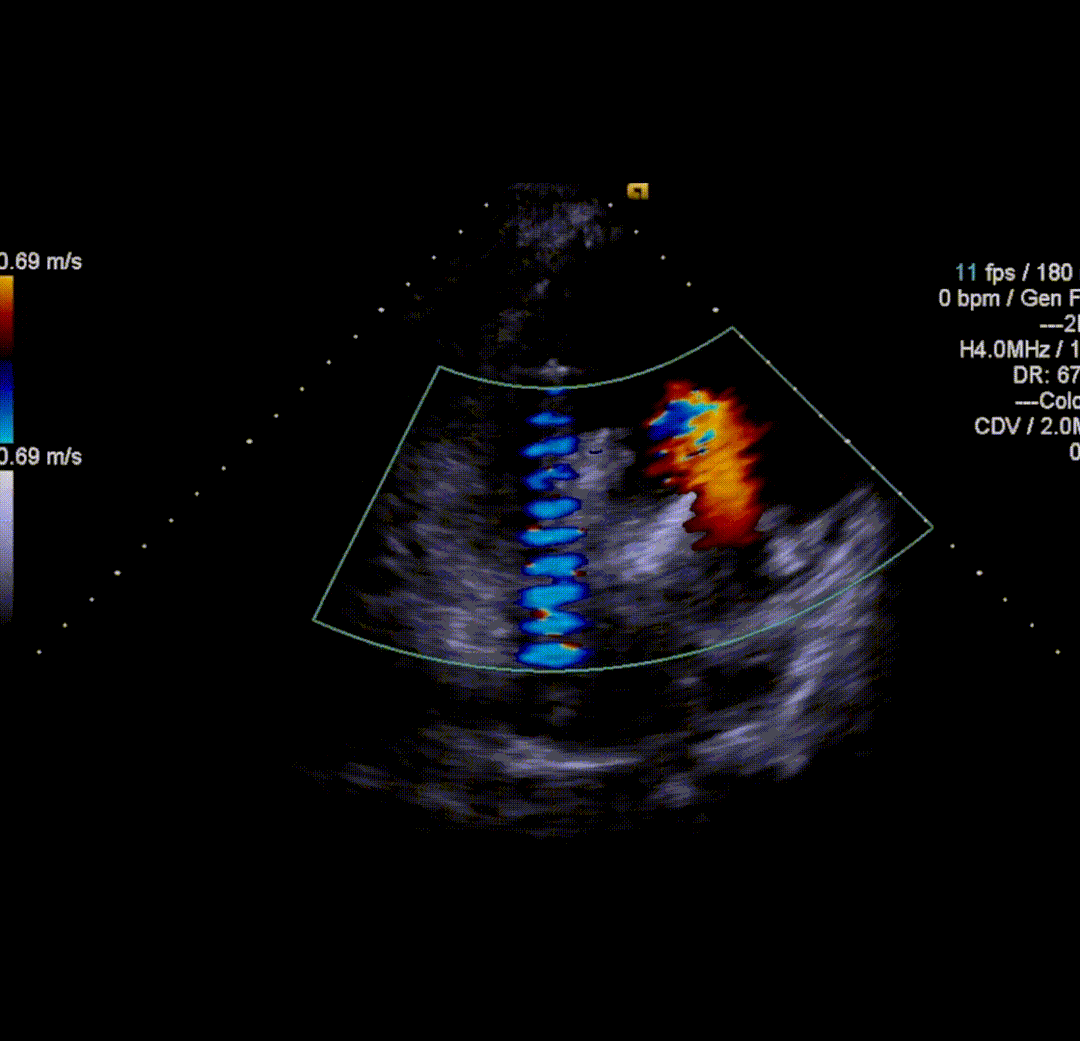

球囊后扩后,瓣膜与周围组织贴合的更好。术后即刻造影结果显示无瓣周漏,工作瓣膜形态优异。术中测量结果显示即刻跨瓣压差降至10mmHg,舒张压从术前35mmHg左右上升到60mmHg以上,术后患者症状明显改善。

术后即刻超声评估